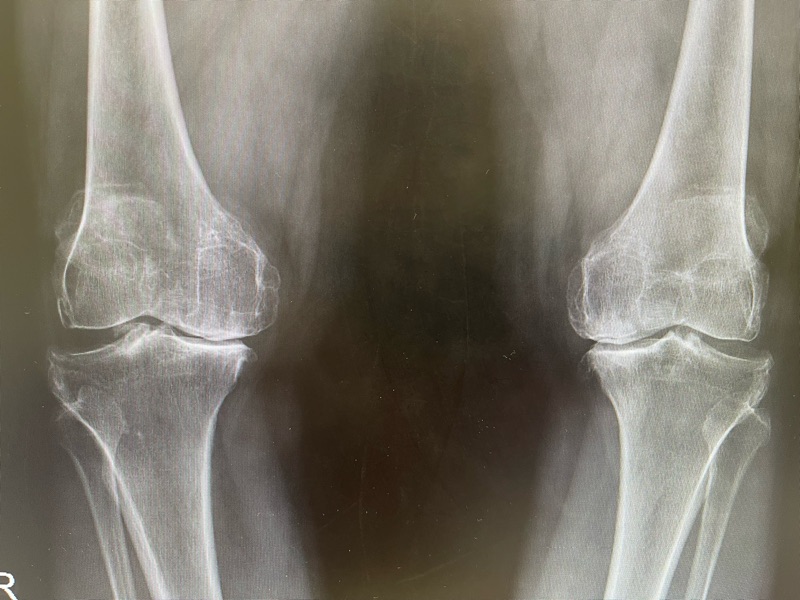

หลังตรวจร่างกายและเอกซเรย์พบว่า ข้อเข่ามีการเสื่อมร่วมด้วย จากการอักเสบสะสมหลายปี ทำให้ผิวข้อบางลง เอ็นรอบ ๆ อ่อนแรง และกระดูกเริ่มเบียดใกล้ชิดกัน

2) เอกซเรย์เข่า

เป็นวิธีที่ใช้บ่อยที่สุด เห็นความแคบของช่องข้อ กระดูกงอก หรือข้อโก่งได้ชัด

- เอกซเรย์เห็นว่าข้อเข่าเสื่อมรุนแรง ผิวข้อหายไปเกือบหมด